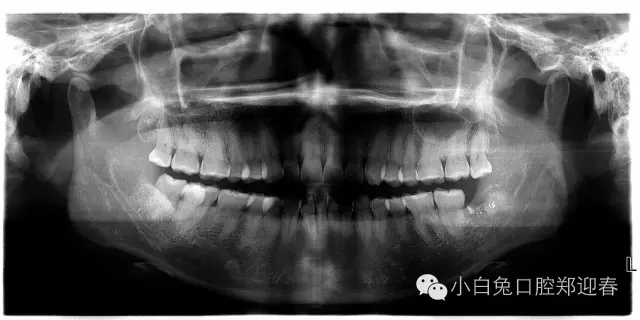

術(shù)前片子

一例智齒斷根進行二次拔除的感悟